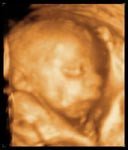

Se lama 4D o 3D en movimiento porque es una ecografía en tres planos con el añadido de la cuarta dimensión, o sea, en tiempo real en movimiento. Gracias a ello se pueden ver gestos faciales del bebé nunca vistos como el bostezo, una sonrisa, el parpadeo o la succión. También se pueden ver claramente los movimientos fetales y valorar el estado de las extremidades, los genitales y otras partes del cuerpo, además de realizar mediciones más precisas.

Además de la función de diagnóstico prenatal, la eco en 3D-4D significa una gran tranquilidad para los padres desde el punto de vista psicológico. Pueden ver al bebé moviéndose con toda precisión lo que supone un impacto emocional muy positivo. Hasta ahora, en la eco normal, los padres sólo veíamos manchas blancas difíciles de interpretar.

Se puede realizar en cualquier momento del embarazo, pero la etapa ideal para poder apreciar bien los movimientos de la cara del bebé es entre la semana 25 y 32. Al igual que la tradicional, los ultrasonidos no suponen ningún riesgo para la madre o el bebé en gestación.